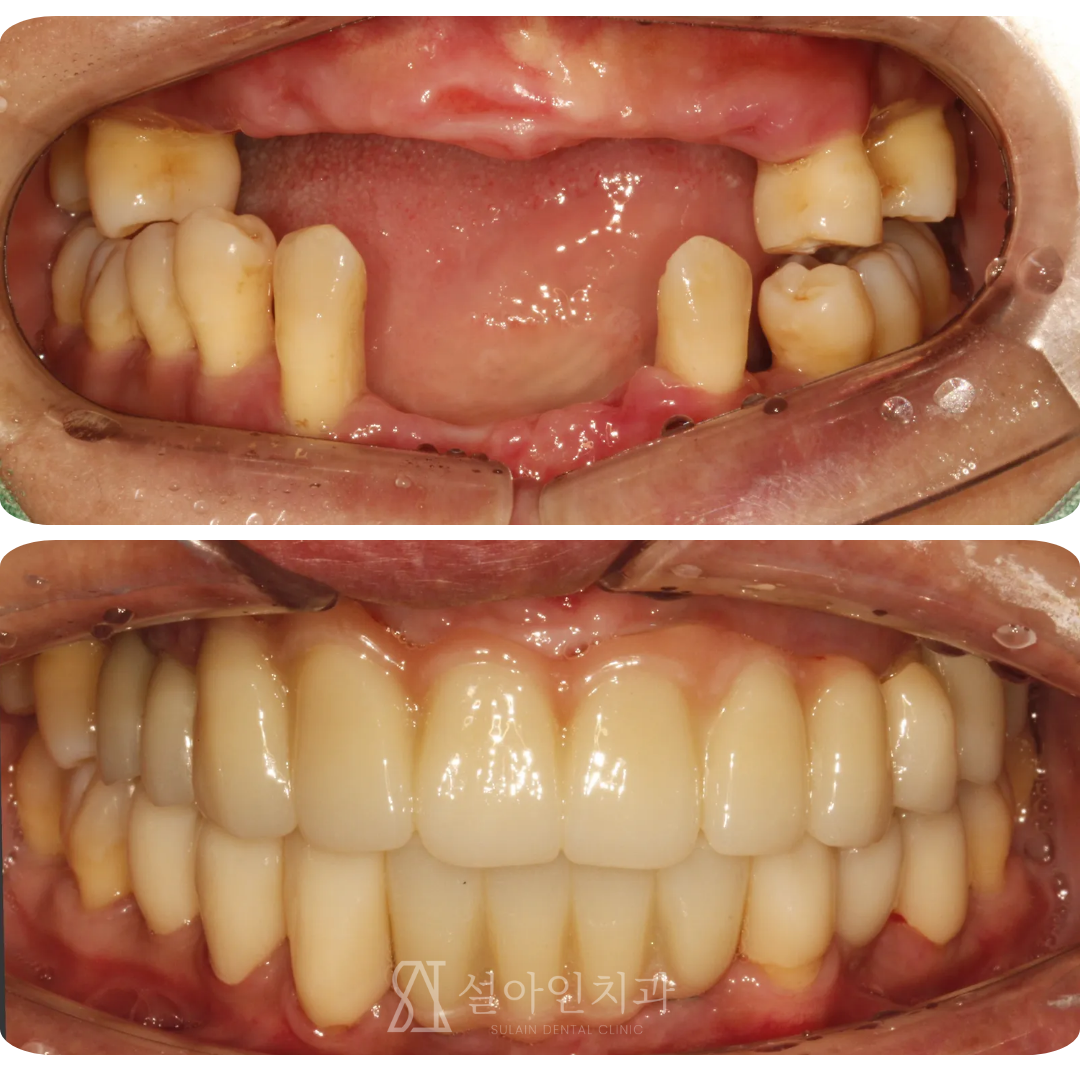

임플란트 수술 다음날, 바로 고정 치아로 식사했습니다. 상악 완전 무치악 환자의 올온엑스(All-on-X) 임플란트 치료 사례